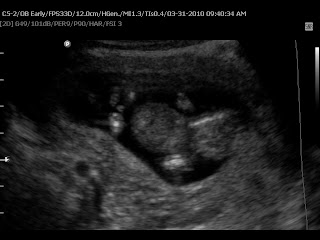

This verse resonated so powerfully with me today as we had our first glimpses of Baby B in our ultrasound. Thankfully everything looks great -- the baby is healthy and growing. We got to see him/her moving all around, hear the heartbeat and see the spine, brain, fingers, toes and just the whole sweet little baby.

I am so thankful to the Lord for the miracle that is life. It astounds me how at four or so inches the Lord has given our baby a heart that beats, a spine, kidneys, a functioning bladder and individual fingerprints. Can you just imagine God figuring out all the intricacies of putting together the first baby? It is the most unique process that no human could ever recreate in a lab with such perfection. Looking at our baby kicking around on the screen I was so full of awe at God for how he makes life. And in awe of the responsibility that he has given Rob and I to care for this precious life.

These pictures are a little small -- they looked bigger on our computer! But you get the idea. :)

Hello sweet baby b!